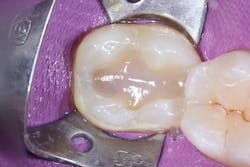

A 26-year-old patient visited a private office for a regular dental checkup. The clinical evaluation showed a No. 18 Class I composite restoration with marginal leakage and infiltration on the distal side of the cavity (figure 1). The surface of the restoration was irregular and lacked dental anatomy. Due to the patient’s esthetic needs and the remaining amount of natural tooth structure, composite filling was selected for the restoration.

The surface anatomy of the restoration was also compromised.